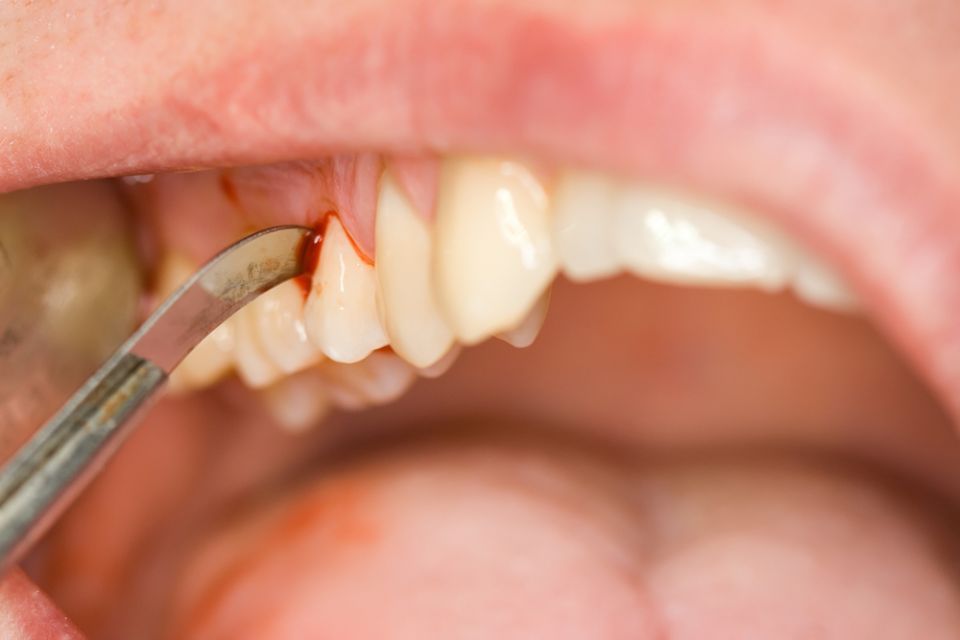

La gingivitis que cursa amb inflamació i envermelliment de les genives i possible sagnat al raspallat.

La periodontitis clínicament presenta els signes de la gingivitis però també s'acompanya de la pèrdua dels teixits que suporten la dent: el lligament periodontal i l'os alveolar, causant-ne la mobilitat de la dent i futura pèrdua si no es tracta.

Les causes de la periodontitis són la combinació de la presència de bacteris patògens juntament amb els factors genètics (resistència de cada persona a les infeccions). A part, se li sumen altres factors que poden condicionar la seva evolució com: tabaquisme, hàbits higiènics, certs medicaments, la diabetis...

El nostre objectiu principal és la prevenció de l'aparició de la periodontitis i en cas de diagnosticar-se, tractar-la per poder eliminar la inflamació i poder aturar-ne la progressió. Per això, és important que el pacient tingui un bon hàbit d'higiene bucal i assisteixi a les revisions i visites periòdiques del dentista.